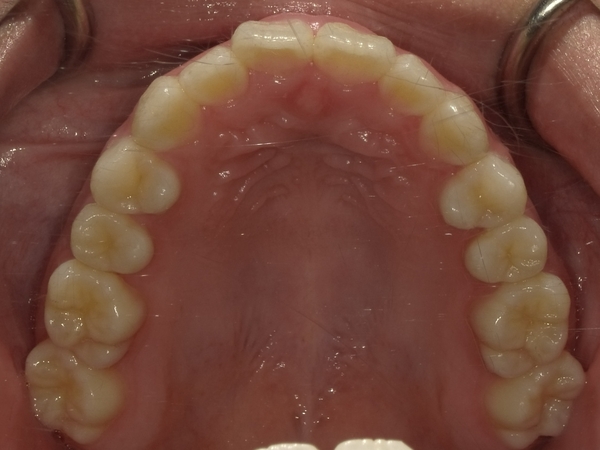

〇ご相談内容:歯のねじれが少し気になる〇矯正の種類:マウスピース型矯正「インビザライン」〇治療期間:14週間〇治療費用:44万円(税込)